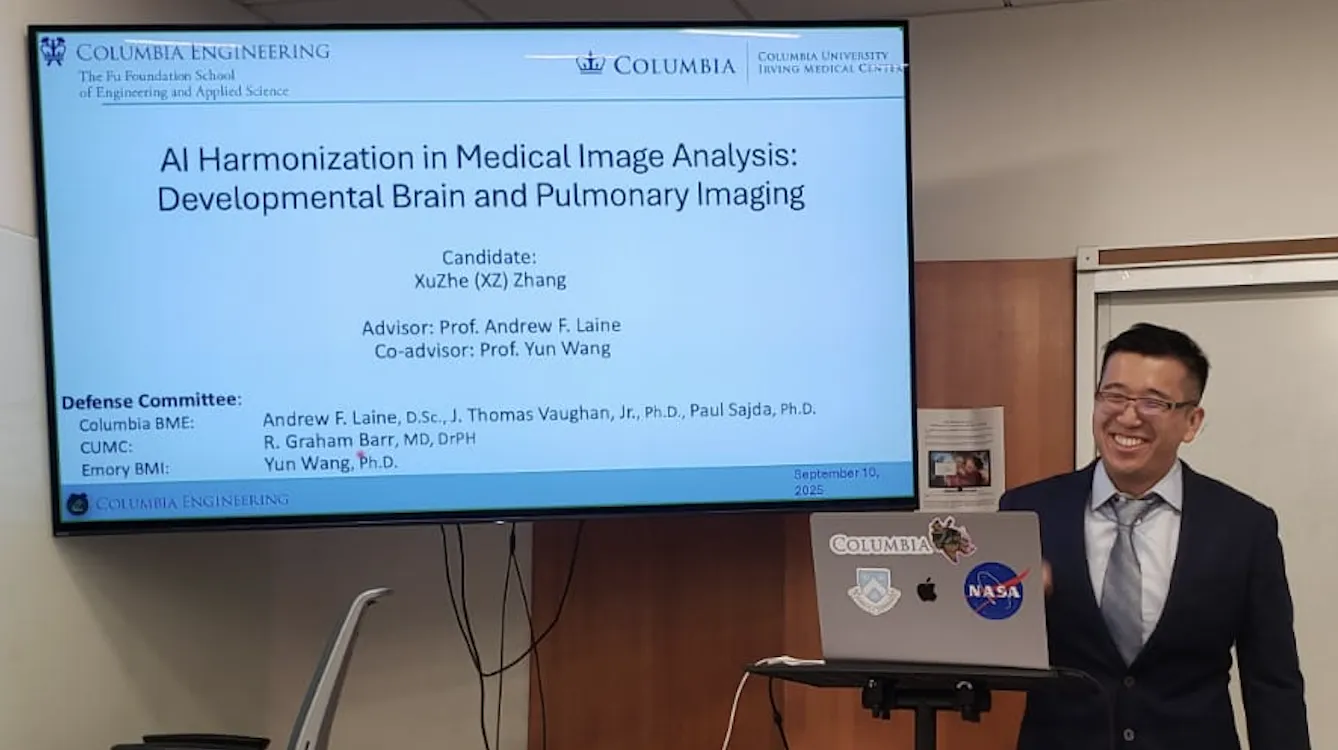

Read more about Xuzhe's thesis on Robust Artificial Intelligence for Medical Image Analysis.